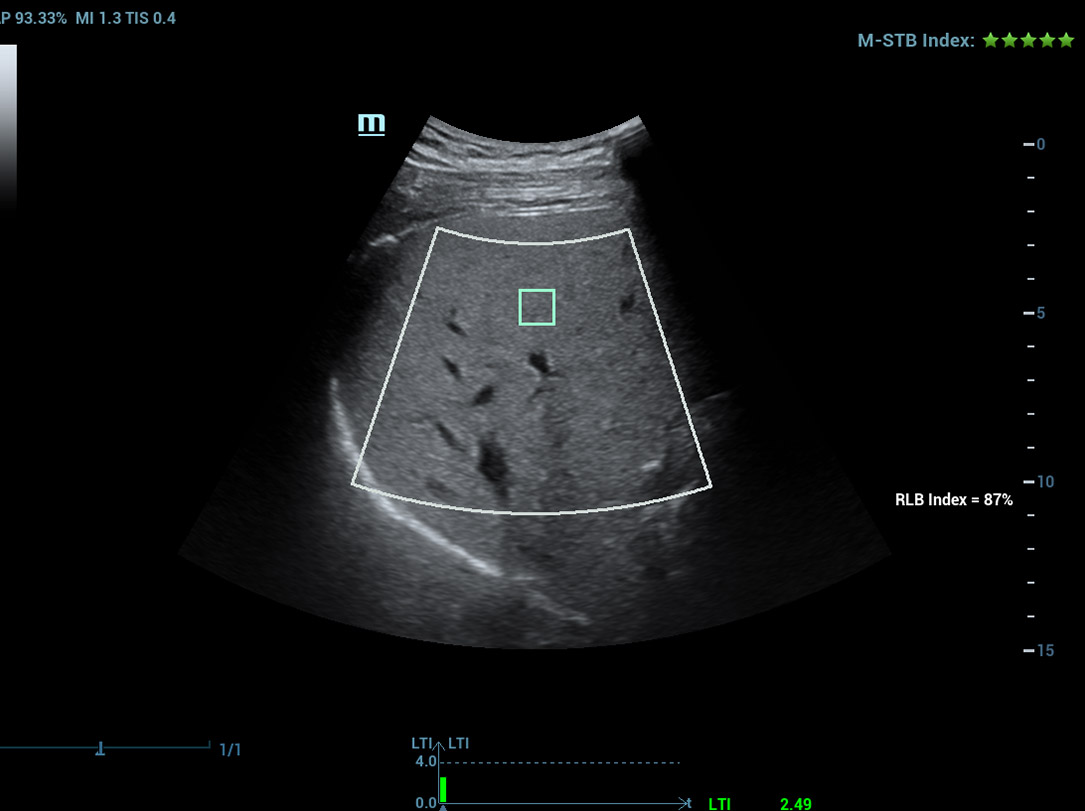

Laboratû°rio multiparamûˋtrico de fûÙgado gorduroso

Um novo salto para a pesquisa sobre esteatose

Laboratû°rio multiparamûˋtrico de fûÙgado gorduroso

O laboratû°rio multiparamûˋtrico de fûÙgado gorduroso oferece vûÀrias ferramentas de anûÀlise quantitativa baseadas em diferentes tecnologias. Permite a anûÀlise quantitativa da esteatose e melhora a sensibilidade na detec??o de fûÙgado gorduroso em estûÀgio inicial.